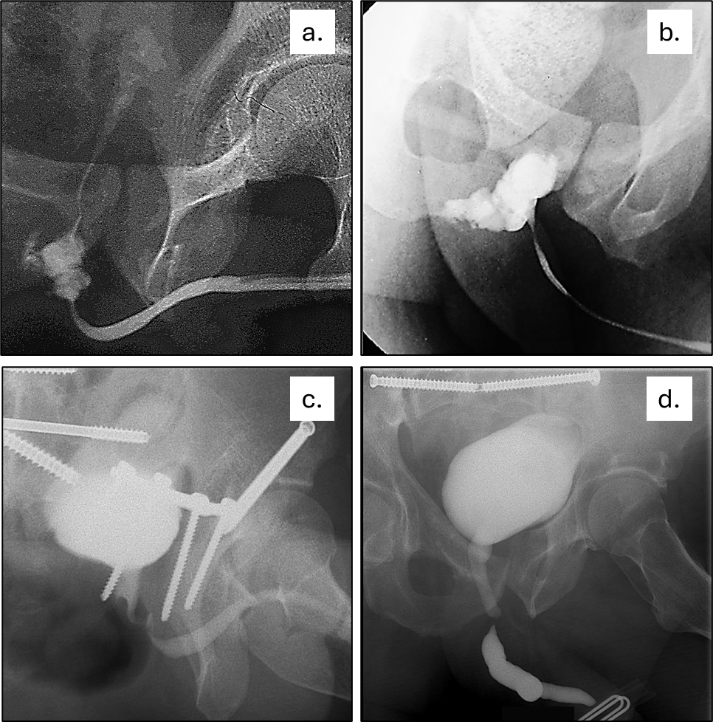

Pueden identificarse tres posibles escenarios en la fase aguda [14,15]: (Figura 4)

- Sin extravasación de contraste: contusión uretral superficial sin interrupción de la submucosa.

- Extravasación con paso de contraste hacia la vejiga: lesión parcial.

- Extravasación sin paso de contraste hacia la vejiga: lesión completa

Fig. 4. Traumatismo uretral.

Fase aguda: a. Lesión parcial; b. Lesión completa.

Fase diferida: c. Lesión no obliterada; d. Lesión obliterada

En esta fase diferida, los pacientes son portadores de una cistostomía como derivación urinaria y para mantener la zona lesionada en reposo mientras cicatriza. En este contexto, al realizar la UCG combinada podemos encontrar dos situaciones (Figura 4):

- Lesión no obliterativa: estenosis con paso de contraste hacia la vejiga.

- Lesión obliterativa: estenosis con ausencia de contraste entre el cabo proximal y el distal.